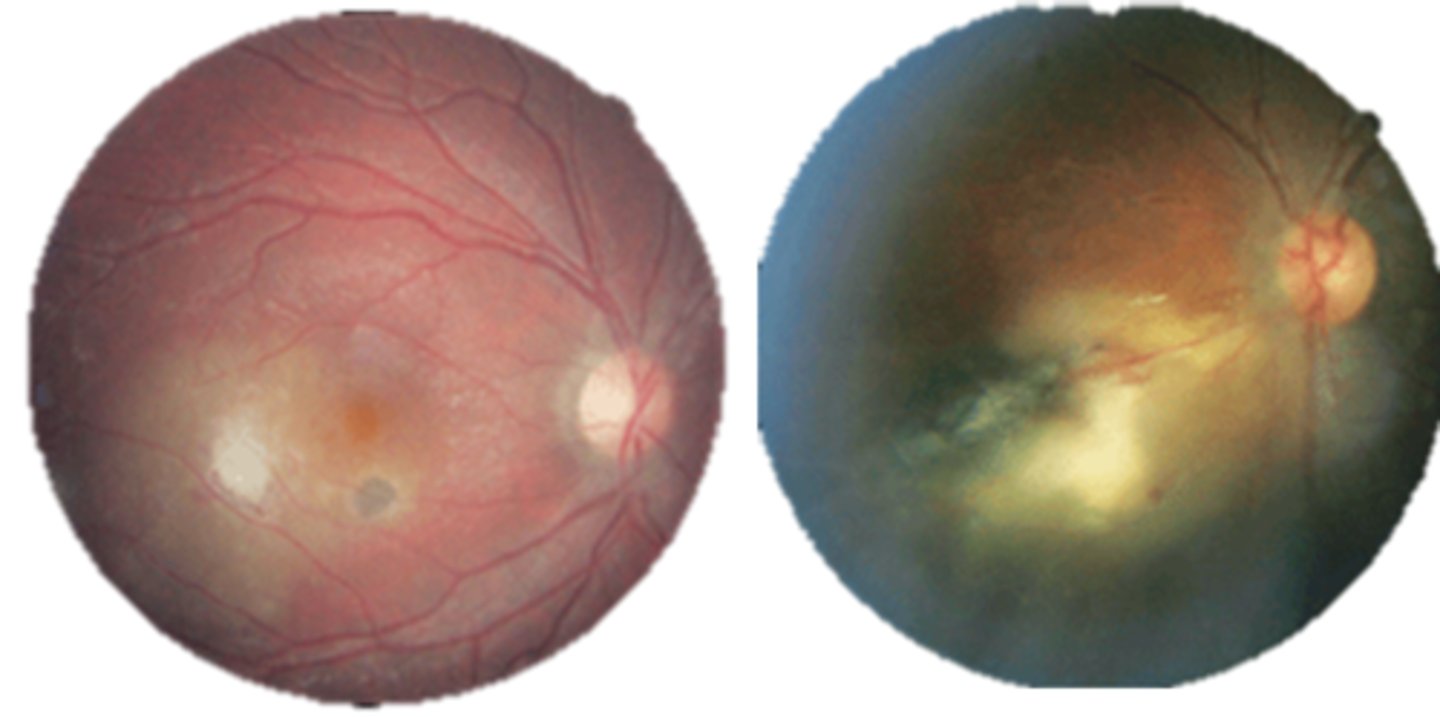

What findings of toxoplasmosis are seen here?

retinal vasculitis

exudative scar

focal, hazy vitritis and retinitis